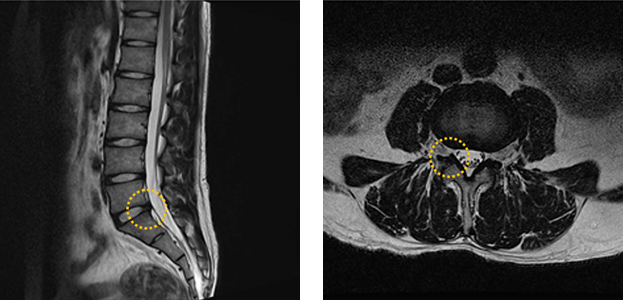

Normal Patient MRI

• Lateral View MRI

• Cross-sectional MRI

Disc Herniation MRI